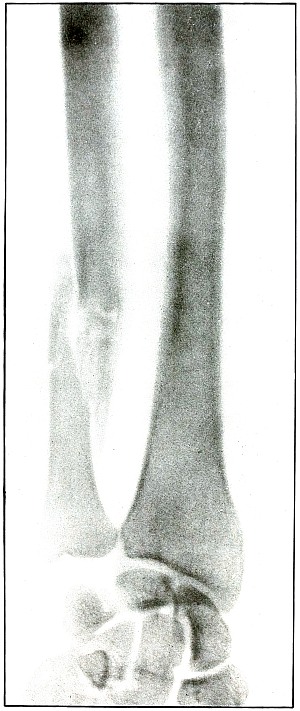

Gunshot fracture, tibia and fibula |

130 |

| 61. |

Gunshot fracture, tibia and fibula |